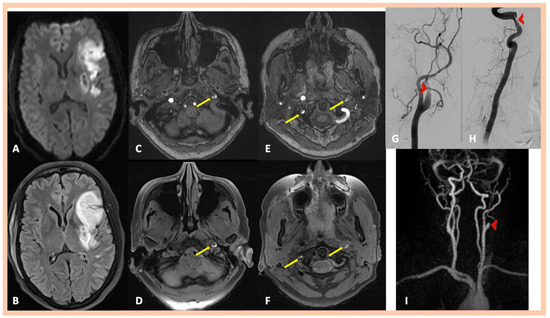

| Pat. #11 | Acute multiple left MCA infarctions | Stenosis along the distal cervical and proximal petrous segments of the right ICA with dissecting pseudoaneurysm along the proximal segment of the right ICA dissection Left internal carotid “flame-like” occlusion, above the bifurcation | Intramural hematoma along the cervical segment of the right ICA Intramural hematoma along the cervical and proximal petrous artery segments of the left ICA | Confirmed MRA findings Mild wall abnormalities and segmental dilatations of the lumen were also observed along the V2 vertebral artery segments bilaterally | Asymptomatic right ICA dissection and symptomatic left ICA dissection | 2 | Mild wall abnormalities of the trunk of the right renal artery, without stenosis, indicative of fibromuscular dysplasia |